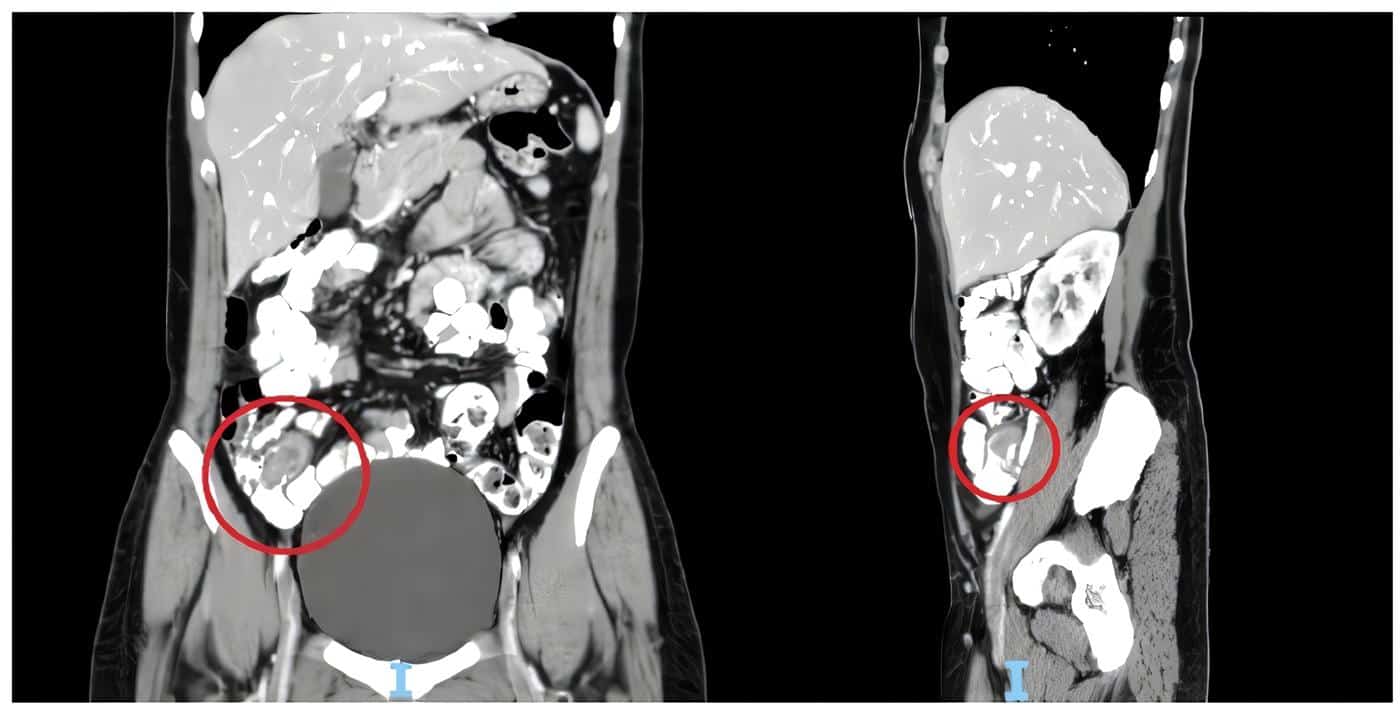

La ecografía transvaginal informó la presencia de ovarios de aspecto poliquístico. El control de las pruebas de laboratorio no mostró elevación de reactantes inflamatorios pero la paciente persistía sintomática, por lo que se realizó una tomografía computarizada de abdomen, en la que se observaron intususcepción del apéndice sobre el ciego y estriación de la grasa pericecal, así como adenomegalias de la cadena ilíaca derecha de aspecto reactivo (figuras 1 y 2).

Figura 1. Tomografía computarizada de abdomen. A la izquierda, corte coronal con signo de doble halo e inflamación de las paredes del ciego sin poder identificar el apéndice. A la derecha, corte sagital donde se observa la invaginación parcial del apéndice hacia el ciego, que impide el ingreso del medio de contraste. Fuente: Elaboración propia de los autores.